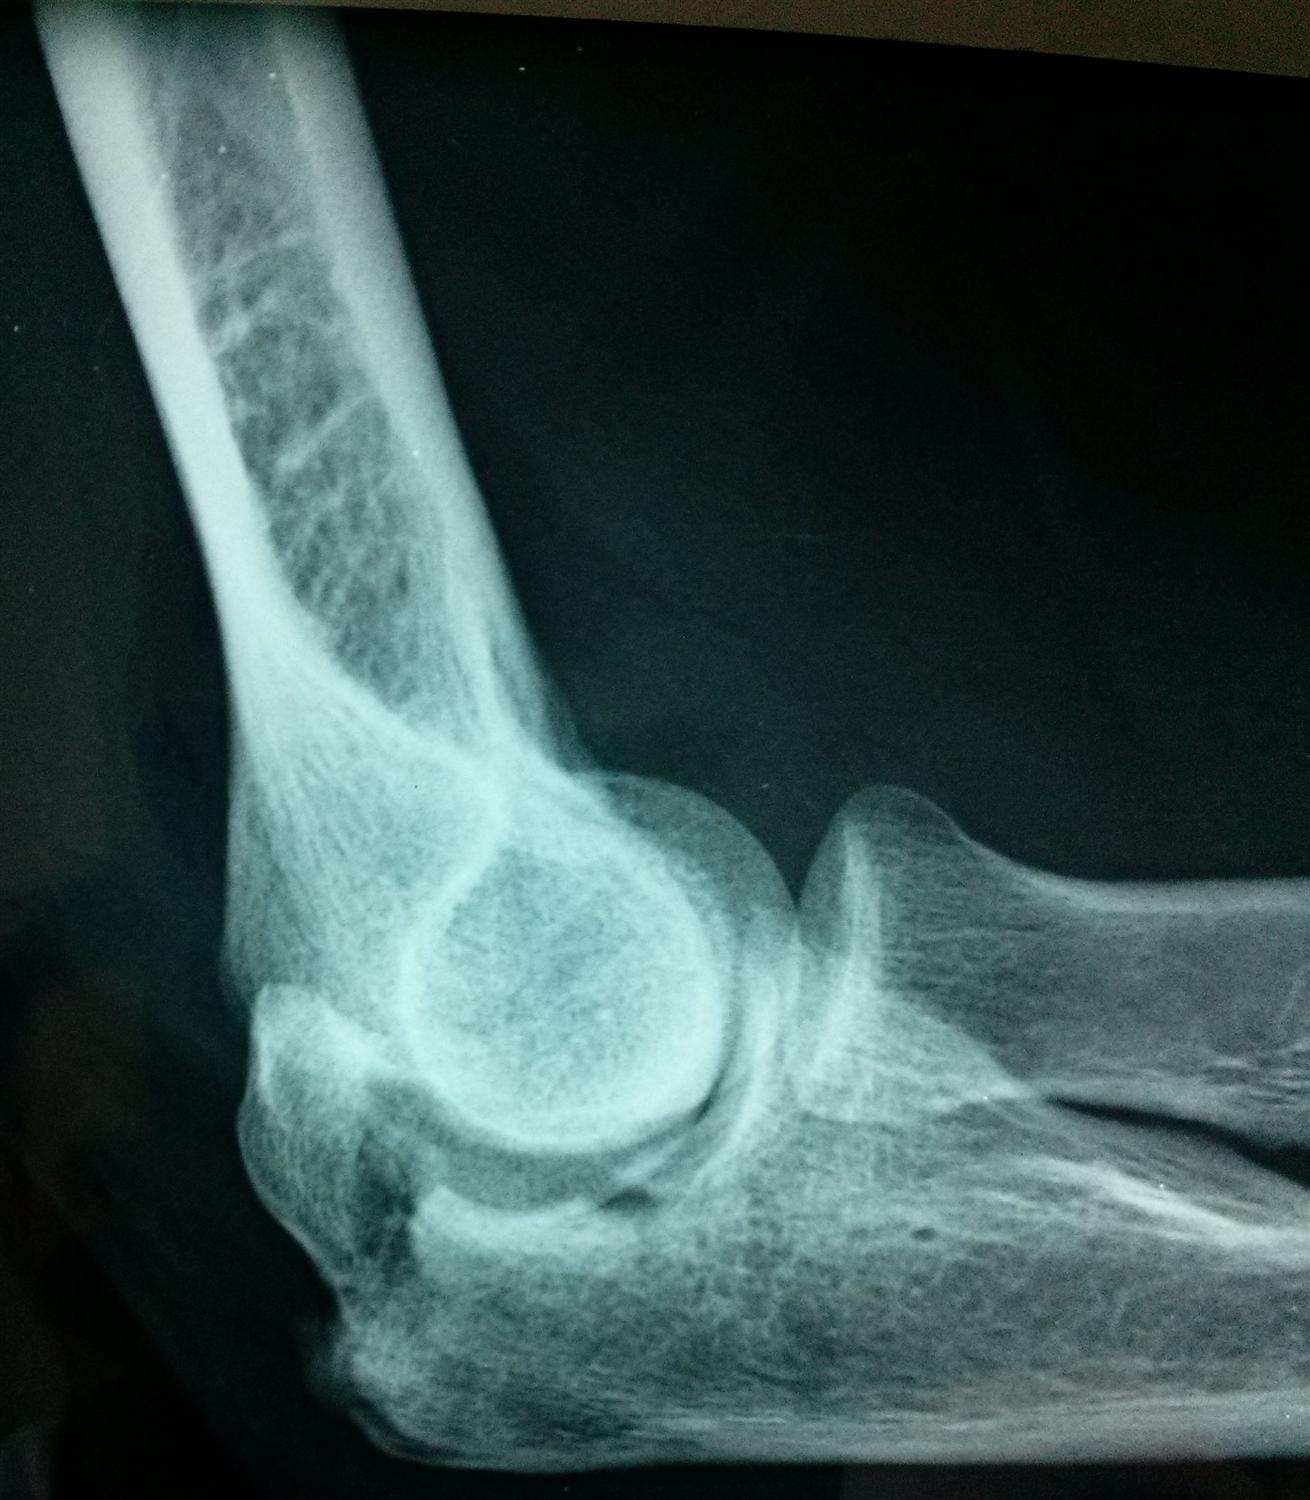

Olecranon fracture Radiology at St. Vincent's University Hospital

Xray Elbow Showing Fracture Proximal Ulna or Olecranon Fracture Elbow Brace Olecranon Fracture Your doctor will use plates, screws, wires, or strong. During this period, it is important. This can help fix the bone and lower the chance of arthritis. An olecranon fracture is usually caused by a fall directly on the elbow. Medically reviewed by cara beth lee, md. You have sustained a fracture to your olecranon (elbow) this normally takes approximately. Elbow Brace Olecranon Fracture.